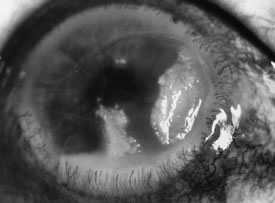

Candida infection typically produces epithelial ulceration, focal necrotizing stromal inflammation, moderate cellular infiltrate and edema in the adjacent stroma, and mild or moderate iritis in the early stages, indistinguishable from bacterial keratitis (Figs. 15, 16, and 17). Fungal elements cannot be detected by biomicroscopy. If untreated, the keratitis evolves to produce dense suppuration and necrosis of the deep stroma. Although multifocal suppuration may develop in polymicrobial keratitis, there is no distinctive sign of mixed Candida and bacterial infection (Fig. 18).

Fig. 17. C. albicans in a 21-year-old woman. Topical proparacaine hydrochloride abuse. Epithelial and stromal ulceration. Note the dense, white area of necrotizing stromal keratitis.